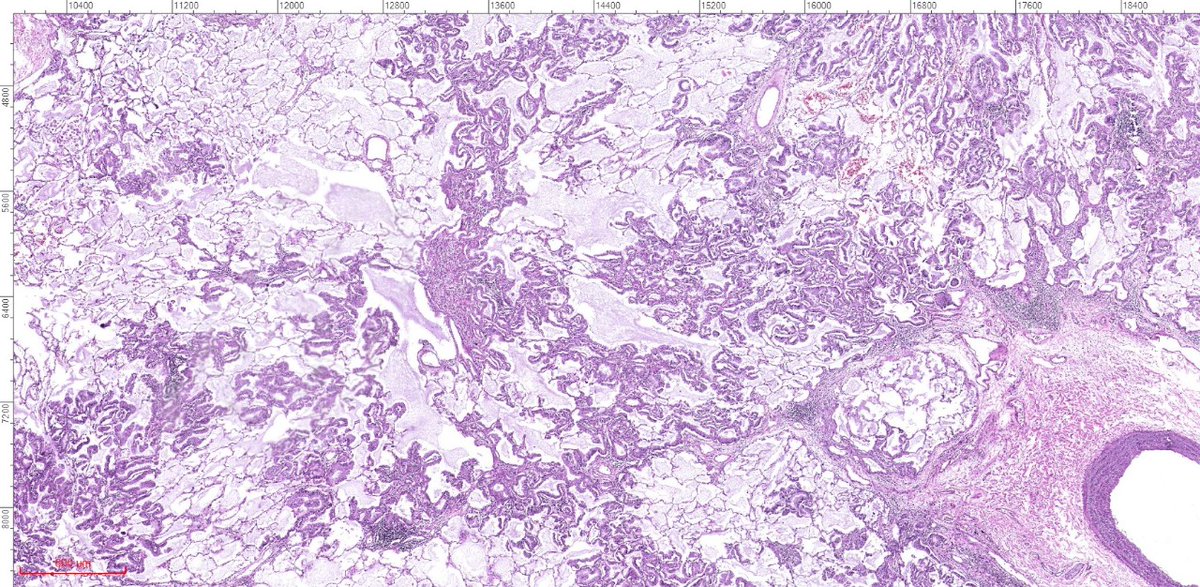

A: Lung Adenocarcinoma (in situ): Images showing emphysematous, lepidic growth pattern w/ increased presence of macrophages in the alveolar spaces, and a close-up of lepidic growing tumor cells around a blood vessel. @LungAssociation @UMRogelCancer #PulmonaryPath #DailyDX